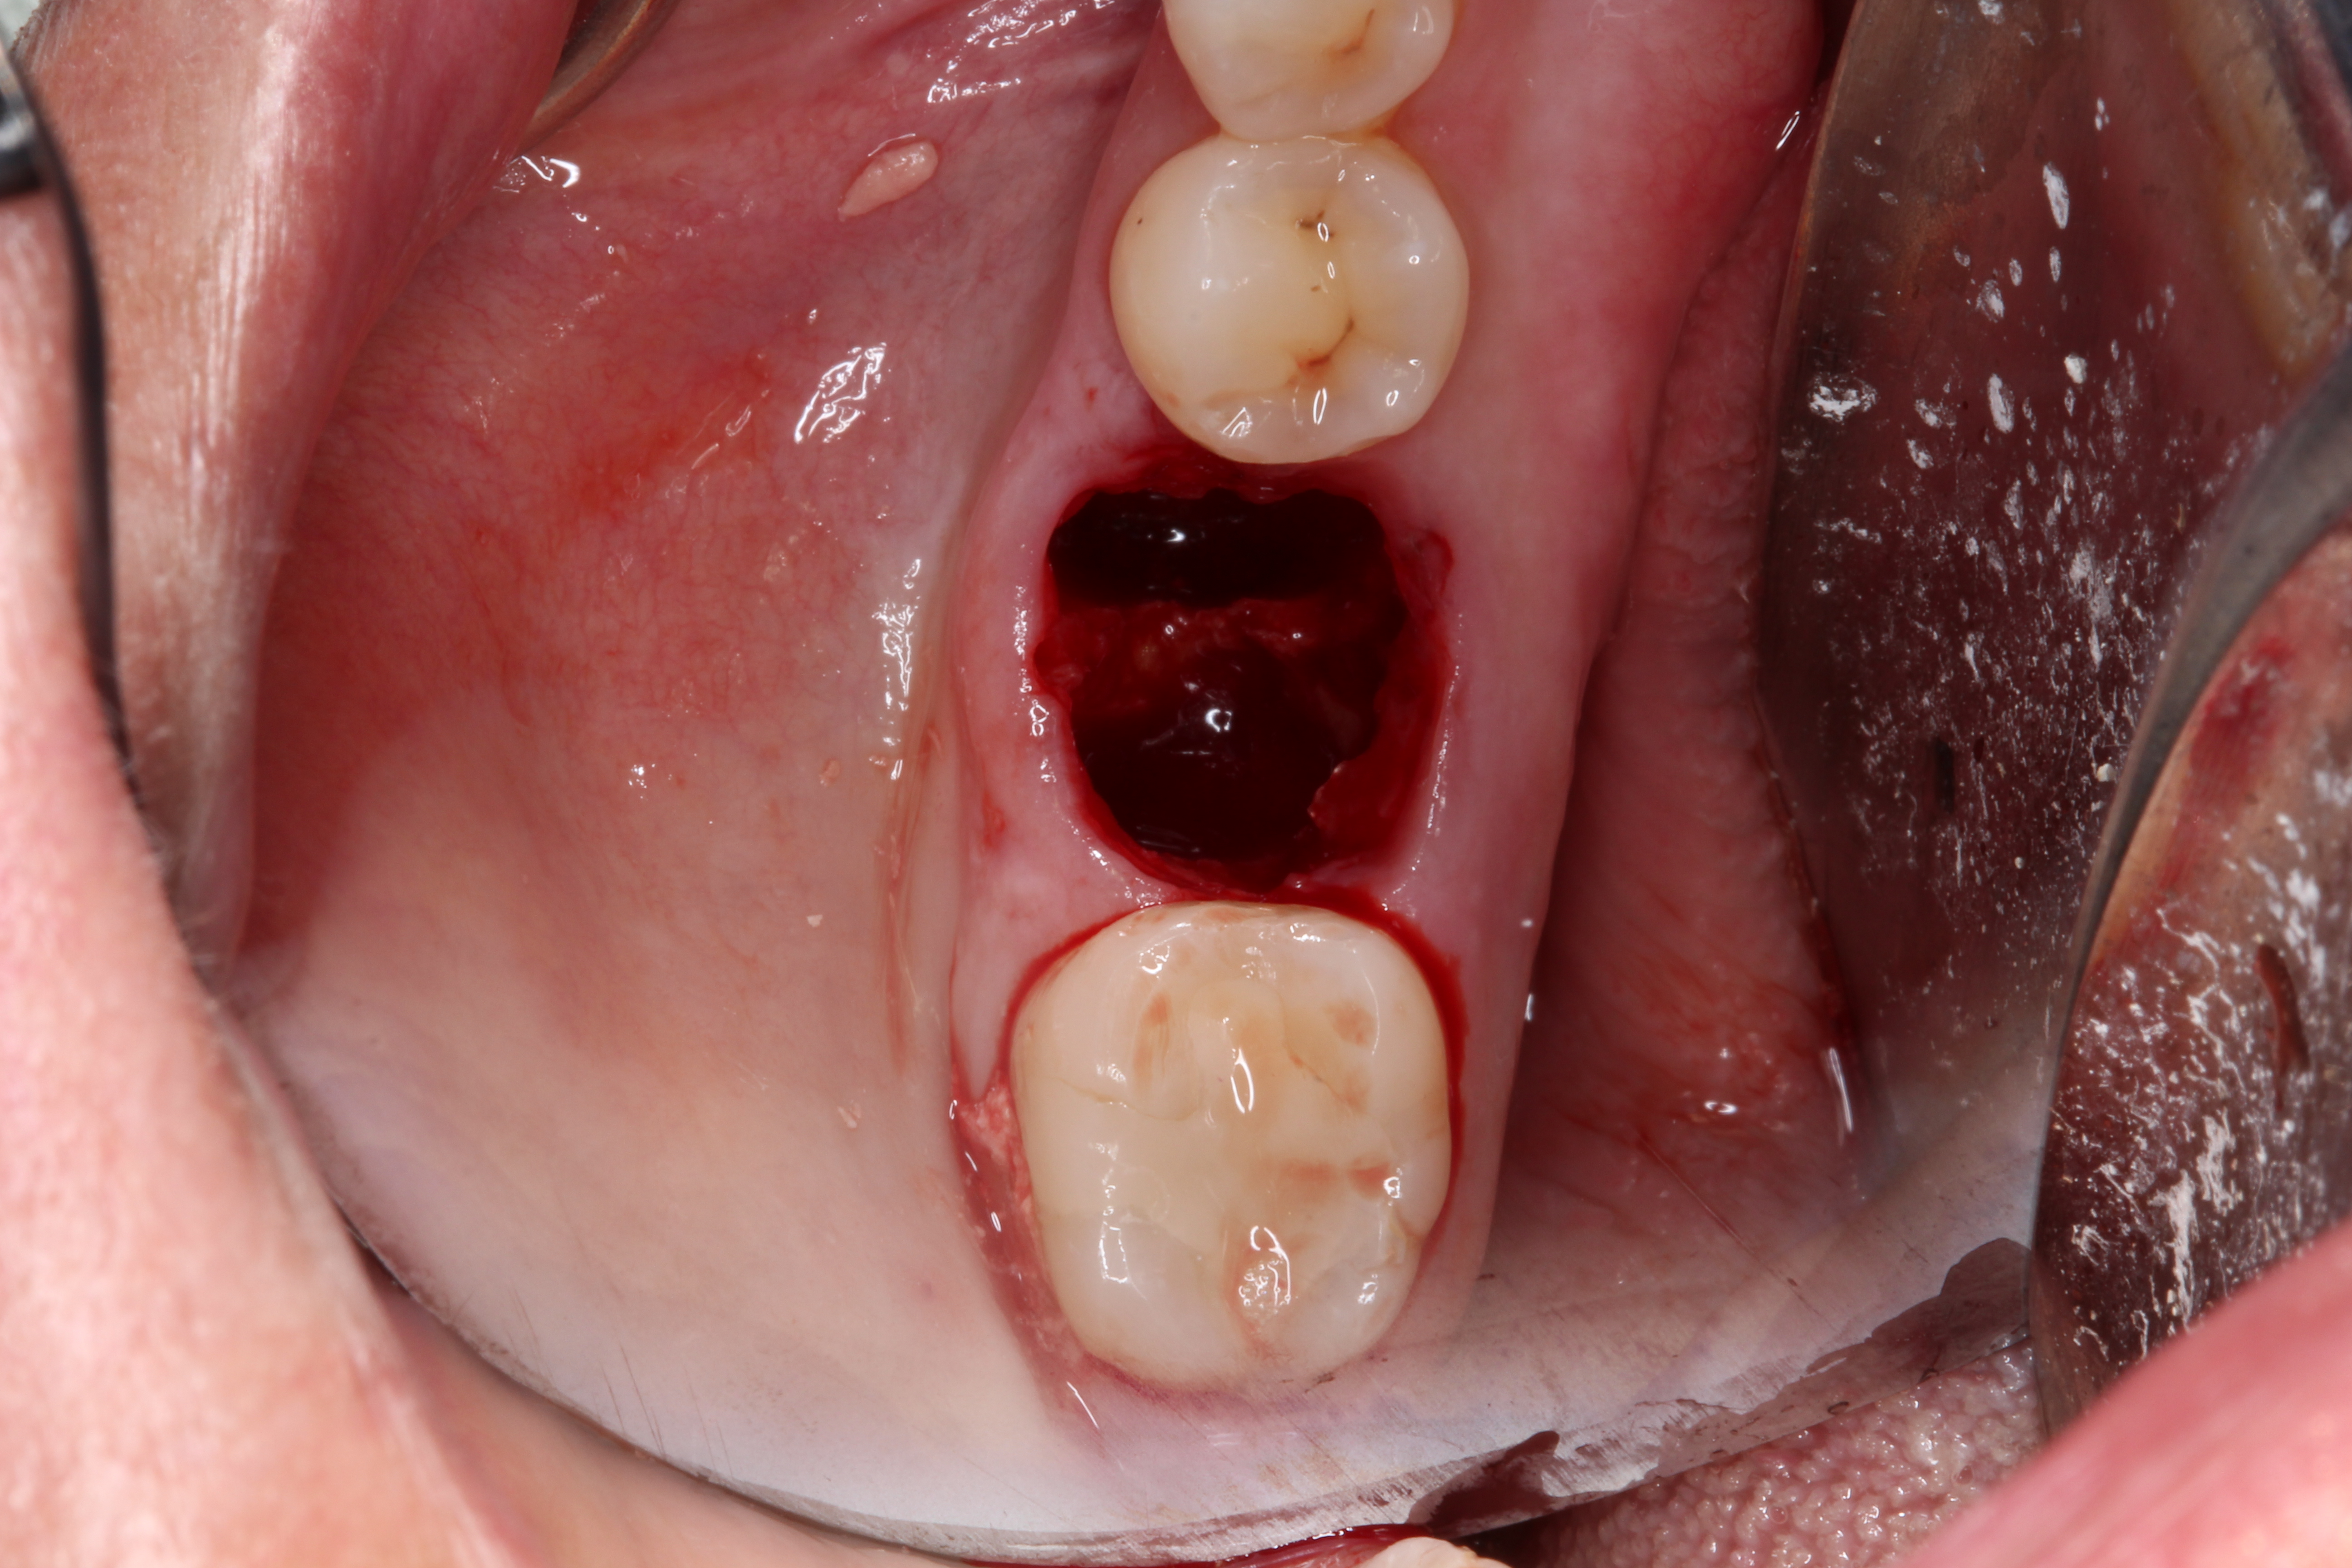

A two-wall defect is also common, usually resulting from the fracture of the buccal plate during the extraction of the tooth. As a result, a barrier membrane is necessary to contain the graft material and decrease the risk for soft-tissue invasion into the graft material (Figure 3).

Fig 3. Example of a large two-wall defect.

Figure 3